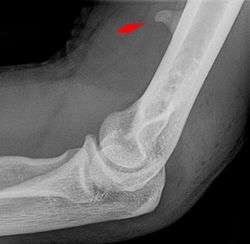

![]() Larger supracondylar process seen on a lateral radiograph of the elbow | |

The supracondylar process of the humerus is a bony projection on the anteromedial aspect of the upper arm bone (humerus), about 5 cm above the medial epicondyle. It is directed downward, forward and medially pointing to the medial epicondyle. It is an anatomical variation which occurs in about one percent of all people. A fibrous band, Struthers ligament, may connect this process to the medial epicondyle.

Supracondylar processes are usually asymptomatic, but may be palpable as a mass on the upper arm. They are most commonly found as an incidental finding on radiographs made for other reasons, but occasionally isolated fractures of the process itself may lead to its discovery. Rarely, presence of the process and a connecting ligament may lead to compression of the brachial artery and the median nerve, leading to pain, paresthesia and/or ischemia.